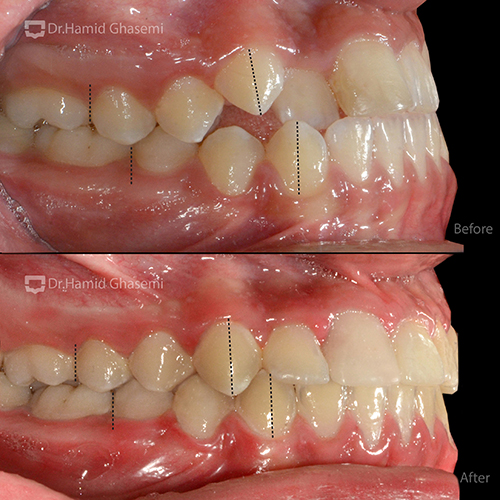

- رابطه کلاس ۳ اسکلتان خفیف و کلاس ۳ دندانی به علت کمبود رشد فک بالا در بعد خلفی قدامی

- رابطه Edge To Edge دندانهای قدامی که منشاء درد در زمان برخورد میباشد

در مرحله اول، با استفاده از اکسپاندر و پیچهای داخل کامی جهت شل شدن درز بین فکی در فک بالا و سپس اعمال نیروی خارج دهانی فیس ماسک جهت جابهجایی فک بالا به سمت جلو انجام شد.

- جابهجایی فک بالا به سمت جلو

- اصلاح رابطه دندانی و فکی همراه با اکلوژن ایدهآل